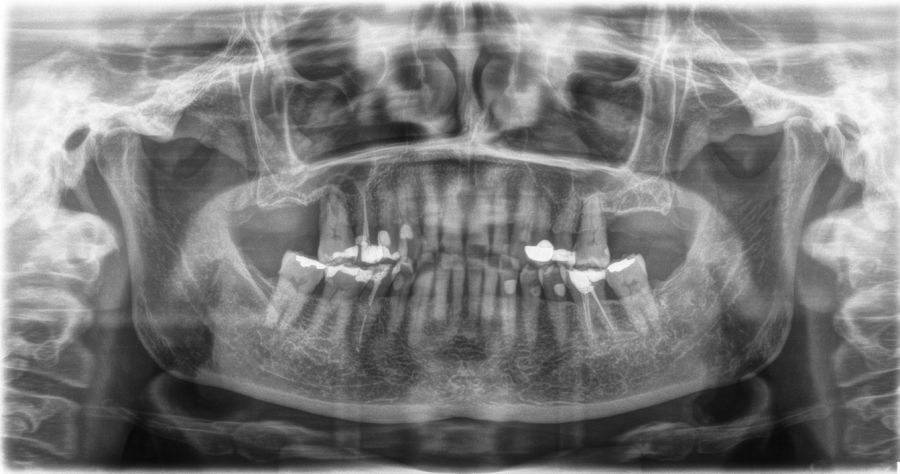

En las Figuras 5-16 se muestra uno de los casos incluidos en el estudio.

Una vez finalizada la cirugía se realiza una radiografía periapical con paralelizador, que se utilizó como punto de partida. Los pacientes acudieron posteriormente para la realización nuevas radiografías de control, tomadas con la misma técnica y sobre las que se realizaron las mediciones necesarias para comprobar la estabilidad y pérdida ósea crestal de los implantes. La medición de la pérdida ósea marginal se realizó en la última radiografía periapical realizada con posicionador de seguimiento. Una vez obtenida la radiografía en formato digital es calibrada mediante un software específico (ImageJ software- Rasband, W.S., ImageJ, U. S. National Institutes of Health, Bethesda, Maryland, USA, https://imagej.net/ij/, 1997-2018) a través de una longitud conocida en la radiografía como es el implante dental. Una vez se introdujo la medida de calibración, el programa informático realiza un cálculo basado en esta medida para eliminar la magnificación, pudiendo realizar mediciones lineales exentas de este error (Figura 2). La pérdida ósea de los implantes fue medida en dos puntos: mesial y distal en cada uno de los casos (Figura 3).

Para la estimación de la ganancia en altura sobre el ápice se realizó un CBCT previo a la carga del implante y al año de carga. Posteriormente, el volumen ganado se monitorizó en las radiografías periapicales al igual que la pérdida ósea crestal.

Fueron reclutados 13 pacientes que cumplieron los criterios de inclusión en los que se insertaron 30 implantes. La edad media fue de 70 +/- 1 años en el momento de la cirugía y 10 de los pacientes fueron hombres. El tiempo medio de seguimiento desde la carga fue de 126 meses (+/- 1,79; Rango 120- 150 meses). Los diámetros, longitudes y posiciones de los implantes se muestran en la Figura 4. La altura media de la cresta residual fue de 4,86 mm (+/-0,97; rango 1,95-5,88 mm). El torque de inserción medio de los implantes fue de 26,45 Ncm (+/- 1,89). Una vez insertados y cargados los implantes, la altura media final fue de 9,68 mm (+/- 2,66; rango 6,74-13,11 mm), lo que supone una ganancia promedio de 5 mm. A los 10 años, se observa una disminución media de la altura ósea ganada en los implantes en conjunto de 0, 29 mm (+/- 0,77).